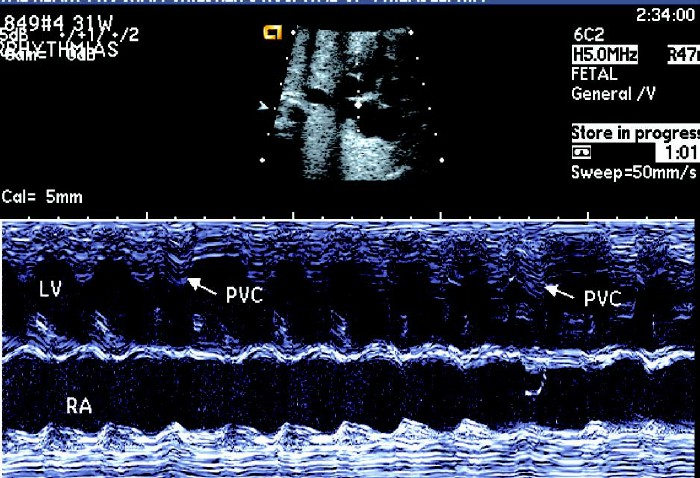

②室性早搏:当心房节律规则,心室收缩提早出现为室性早搏,室早不影响窦房结节律,故室性早搏的波形后方出现完全性代偿间歇,由于心室充盈不足,多普勒频谱峰值低于正常。